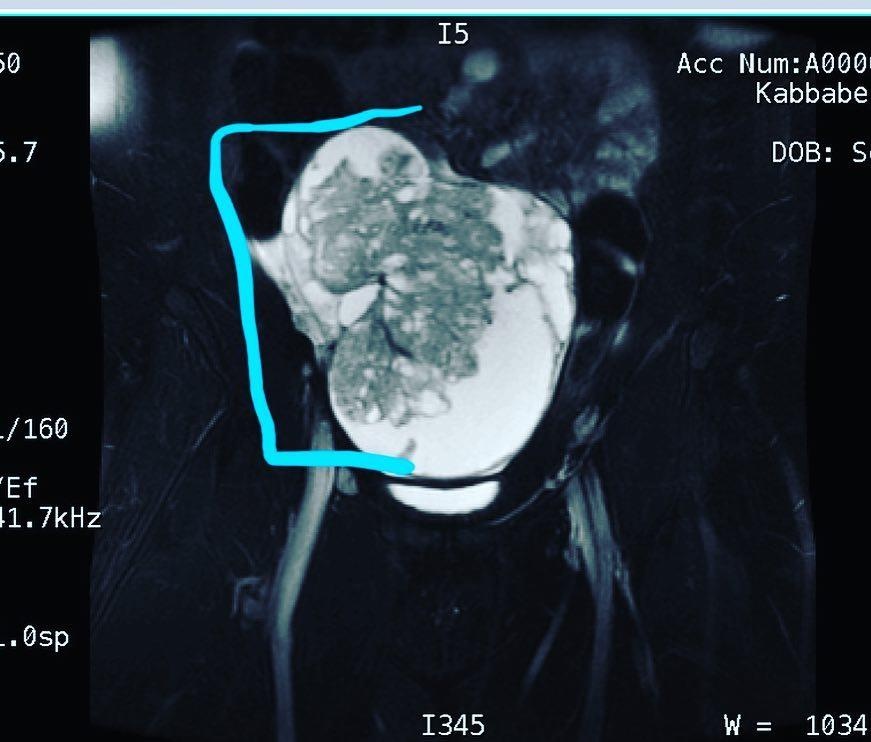

Vào cuối tháng 10/2017, Kabbabe cuối cùng phải nhập viện cấp cứu sau khi toàn bộ cơ thể cô bị đau như có ai đó đánh mạnh vào bụng. Vài tuần sau, sau nhiều lần siêu âm, cuối cùng cô được chẩn đoán mắc bệnh ung thư buồng trứng. Trên thực tế, khối u của cô có kích thước gần bằng một quả dưa lê.

| Khối u ung thư buồng trứng của Kabbabe có kích thước bằng quả dưa lê. Ảnh: Dailymail. |

Khối u Kabbabe mắc phải là khối u tế bào mầm buồng trứng ác tính, khi ung thư hình thành trong các tế bào trứng của buồng trứng. Theo Hiệp hội Ung thư Mỹ, chỉ có 2-3% trường hợp ung thư buồng trứng là khối u tế bào mầm.

Kabbabe được phẫu thuật vào tháng 11/2017 tại Trung tâm Memorial Sloan Kettering để loại bỏ khối u, buồng trứng phải và ống dẫn trứng bên phải. Khối u của cô có kích thước bằng quả dưa lê và rộng 18 cm.